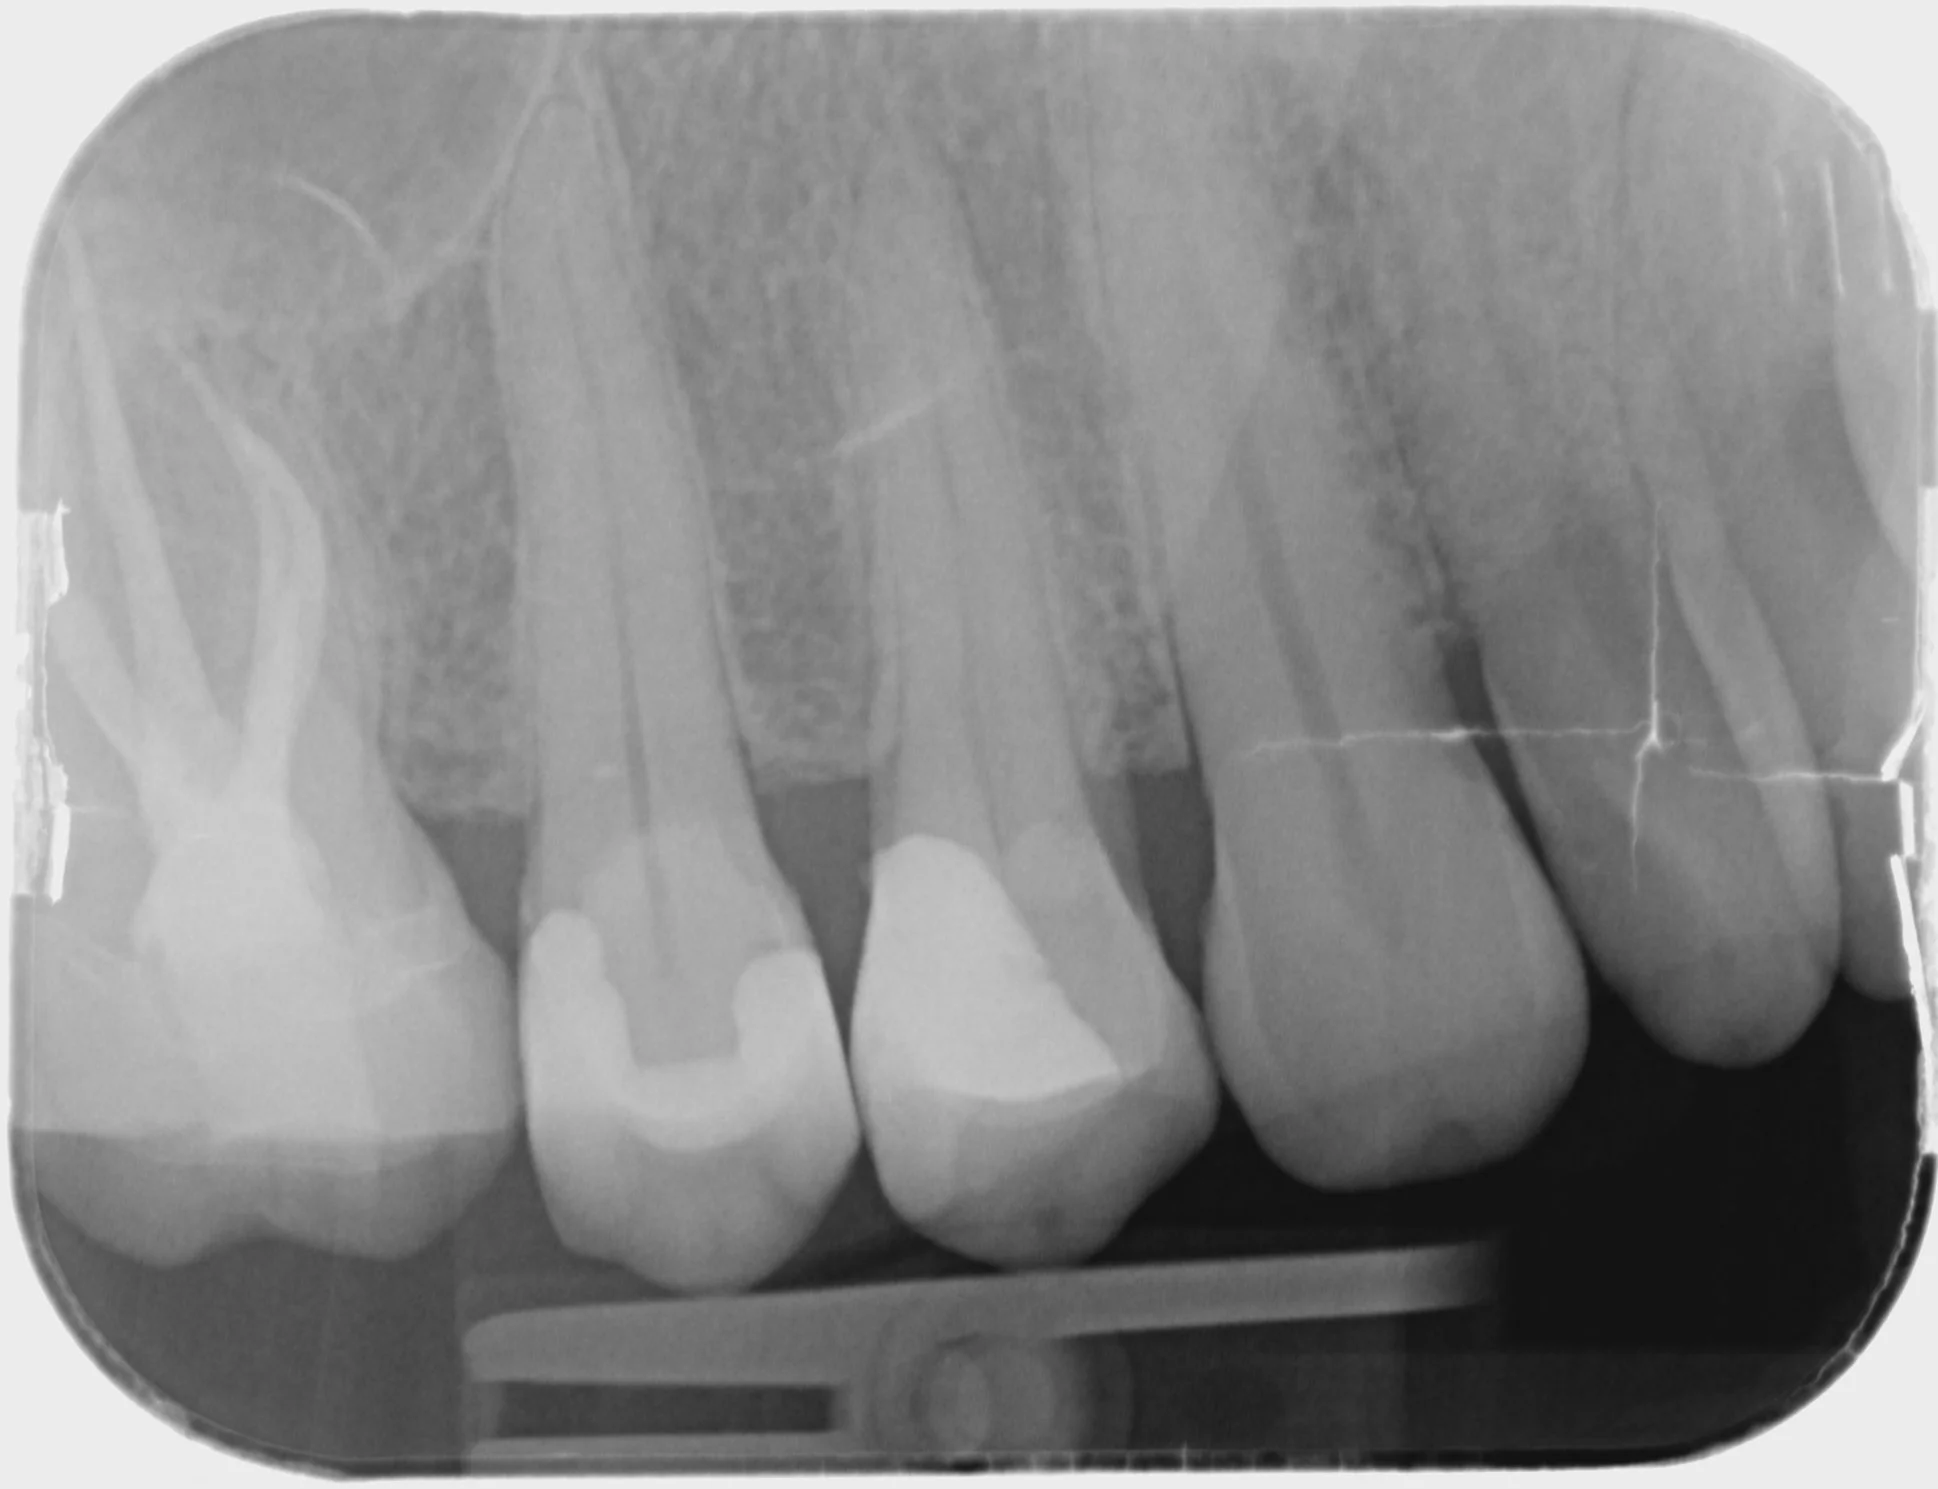

Endodontics